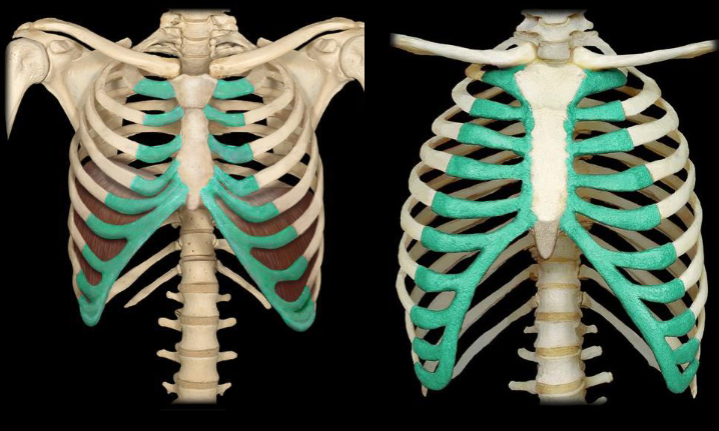

What bone is highlighted in this image?

What type of ribs are highlighted in this image?

What type of ribs are highlighted in this image?

What type of ribs are highlighted in this image?

What bone is highlighted in this image?

costal cartilage (medial, touching the sternum)